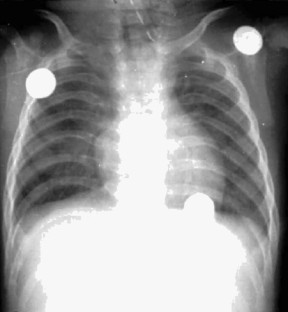

Herman, T., Siegel, M. Feingold Syndrome: Microcephaly, Esophageal Atresia, Type III Laryngeal Cleft, Malrotation, Limb Anomalies. J Perinatol 24, 568–570 (2004). https://doi.org/10.1038/sj.jp.7211144